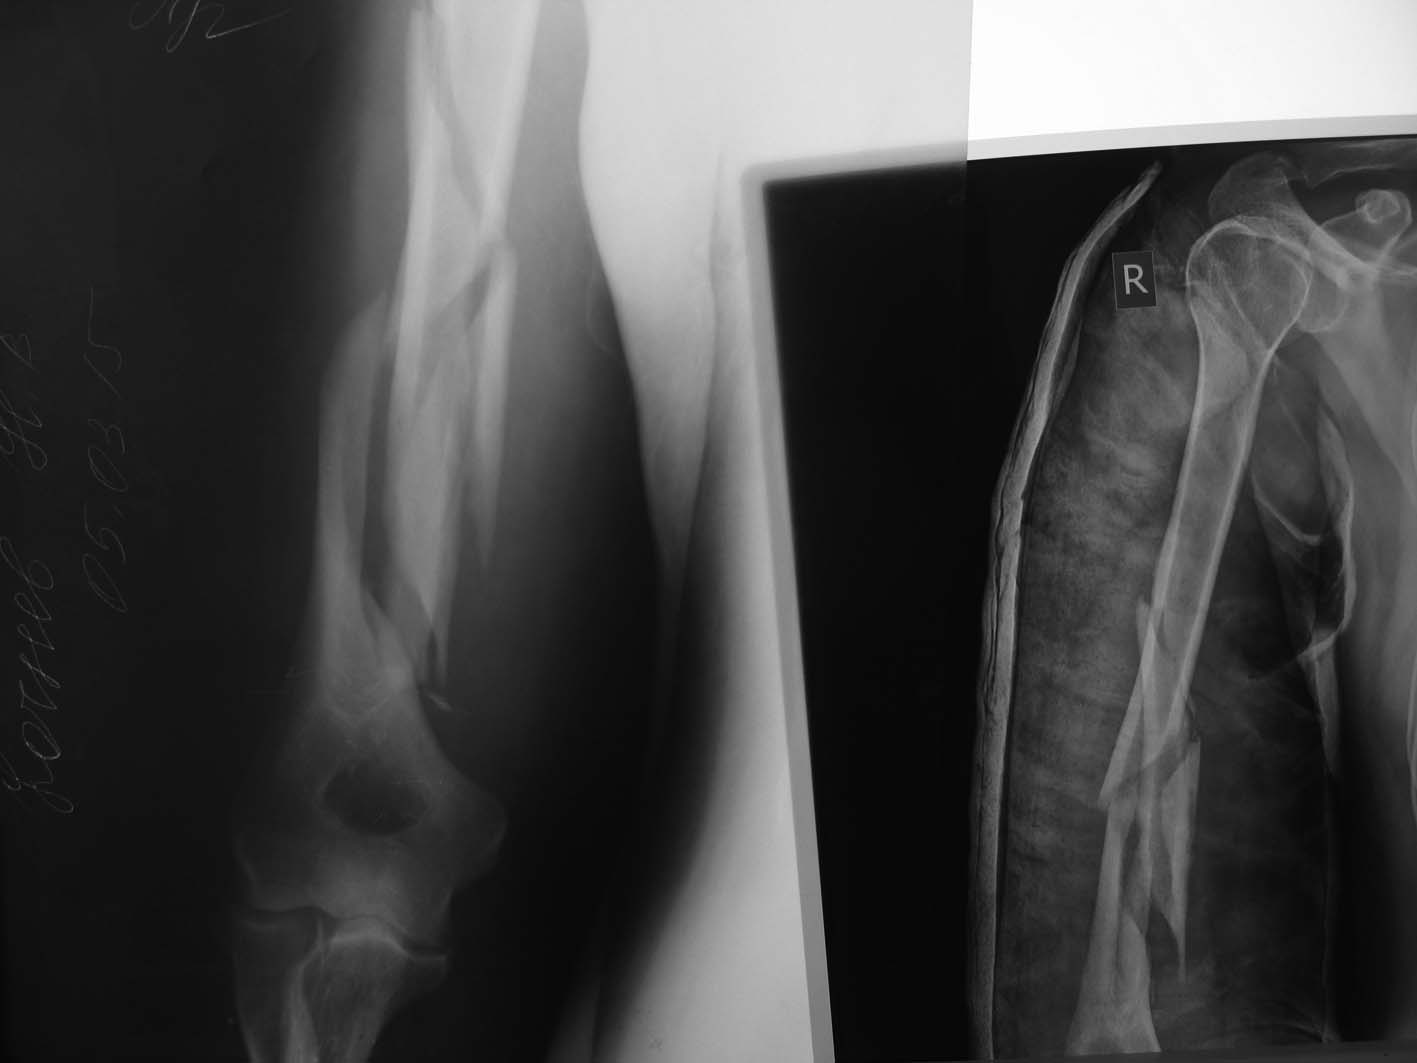

[Ortho] Оскольчатый перелом плеча

Первичный снимок и контроль(13.03.14) в циркулярной гипсовой повязке